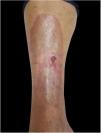

A 62-year-old female patient presented an ulcerated, hyperkeratotic lesion in the NL area, on the right leg, about three months prior, with no history of local trauma. She had been diagnosed with NL in the pre-tibial region of both legs ten years before, with no history of recurrent ulceration. The patient had controlled systemic arterial hypertension and type 2 DM. She used oral hypoglycemic agents, with good control in the last years, and did not present retinopathy or diabetic nephropathy. At the physical examination, the patient presented atrophic bilateral plaques on the pre-tibial region and, on her right leg, a small hyperkeratotic ulcerated plaque over a NL lesion (Fig. 1). The anatomopathological examination showed a moderately differentiated SCC with invasion of the reticular dermis in an NL lesion (Figs. 2 and 3). No palpable lymphadenomegalies were observed. The SCC was excised and the wound was closed with a graft. The patient evolved well in the immediate and late postoperative period. The anatomopathological examination showed tumor-free margins.